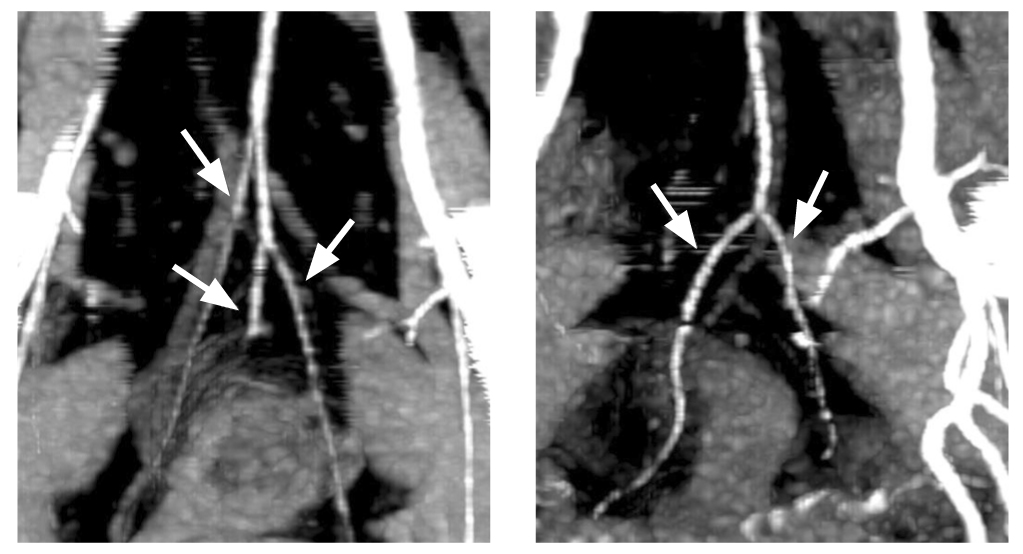

Рис. 4. Три ветви верхней прямокишечной артерии в момент отхождения (стрелки). Классический (1-й тип) анатомии верхней прямокишечной артерии.

Рис. 5. Три ветви верхней прямокишечной артерии до бифуркации (стрелки). Классический (1-й тип) анатомии верхней прямокишечной артерии.

Следует отметить, что в 1/3 (34%) случаев определялось по 2 ветви верхней прямокишечной артерии с последующей трифуркацией, причём задние ветви отходили в виде дуг к задней стенке кишки на 5 и 7 часах условного циферблата — вариант 2. На рис. 6 изображены первый и второй варианты. Так же редко, всего в 2 наблюдениях, отмечалась сосудистая аркада в виде дуги, питающая почти всю окружность кишки по типу кровоснабжения тонкого кишечника — вариант 3 (рис. 7). Чуть более часто, в 6 случаях, наблюдался рассыпной тип с одновременным или последовательным отхождением от верхней прямокишечной артерии 6 отдельных ветвей к стенке кишки — вариант 4 (рис. 8). В 4% случаев наблюдалось по 4 ветви верхней прямокишечной артерии, 2 из которых формировали бифуркации, а 2 шли отдельно — вариант 7.

Рис. 6. Трифуркация верхней прямокишечной артерии слева и бифуркация верхней прямокишечной артерии справа (стрелки). Реконструкция компьютерной томографии.